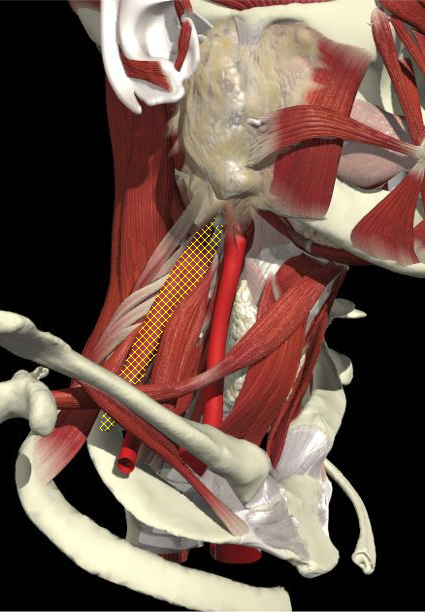

ACCURACY OF LOCALIZATION - SCALENES

ACCURACY OF LOCALIZATION LEVATOR SCAPULAE

LOCALIZATION OF MUSCLES IN DEEPER LAYERS

Layer 1

Layer 2

Layer 3

Splenius Capitis

Semispinalis Capitis

Longissimus Capitus

Semispinalis Cervicis

ACCURACY OF LOCALIZATION – DEEPER LAYERS